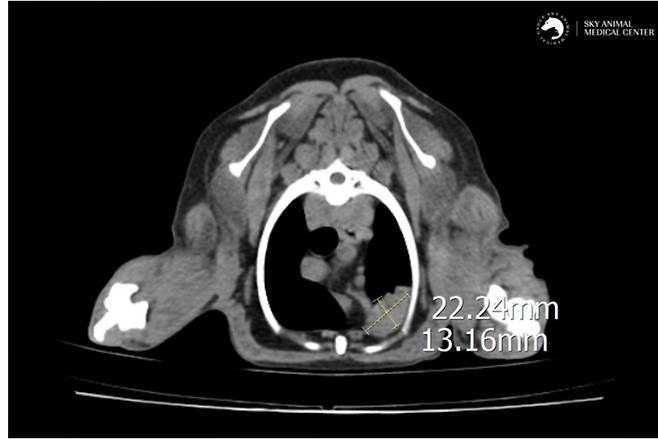

의료진은 피부 종괴보다 폐 병변이 더 시급한 문제라고 판단했다. 보호자와 상의 끝에 종양의 정확한 상태와 전이 여부를 확인하기 위해 CT(컴퓨터 단층촬영) 검사를 진행했다.

검사 결과, 폐 좌측 전엽에서 종양이 의심되는 소견이 발견됐다. 다행히 복부 내 장기에는 전이는 없었으나, 종괴가 크고 이로 인한 무기폐(폐 부피가 줄어든 상태)가 확인됐다.

전이될 위험성이 높고 종괴가 한 엽에 국한돼 있어 수술 후 예후가 좋을 것으로 판단됐다. 이에 보호자와 협의해 폐엽 절제 수술을 진행하기로 했다.